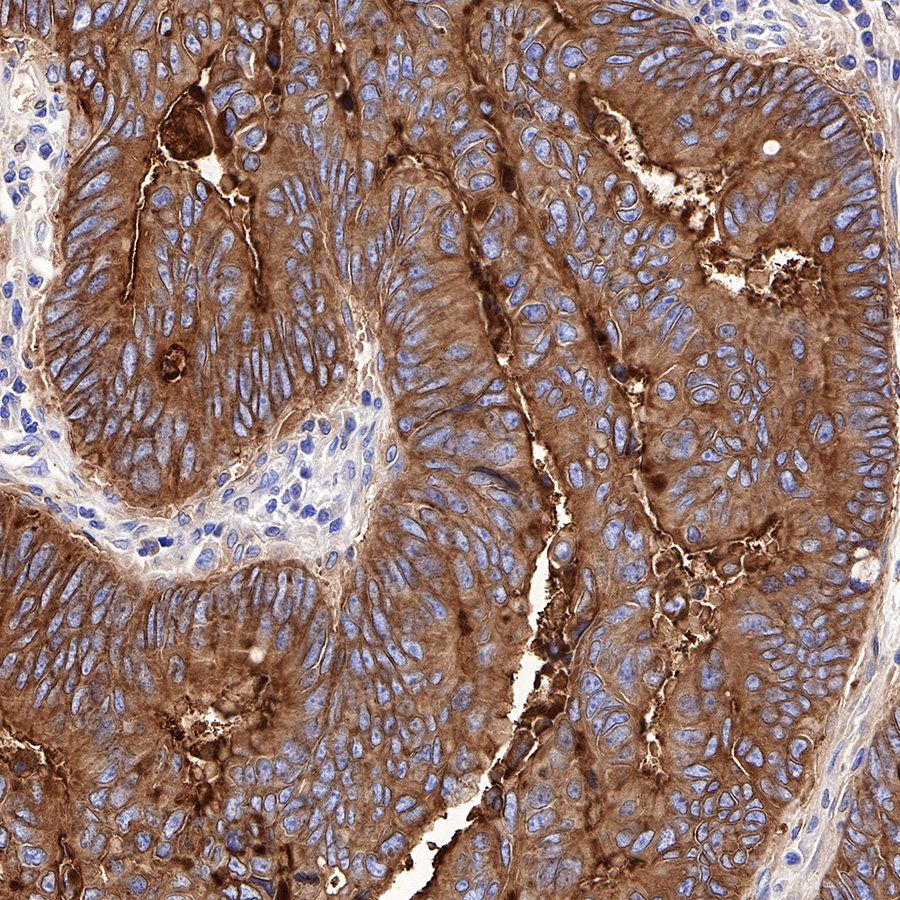

IHC shows positive staining in paraffin-embedded human colon. Anti-CEA(CD66e) antibody was used at 1/1000 dilution, followed by a Goat Anti-Rabbit IgG H&L (HRP) ready to use. Counterstained with hematoxylin. Heat mediated antigen retrieval with Tris/EDTA buffer pH9.0 was performed before commencing with IHC staining protocol.